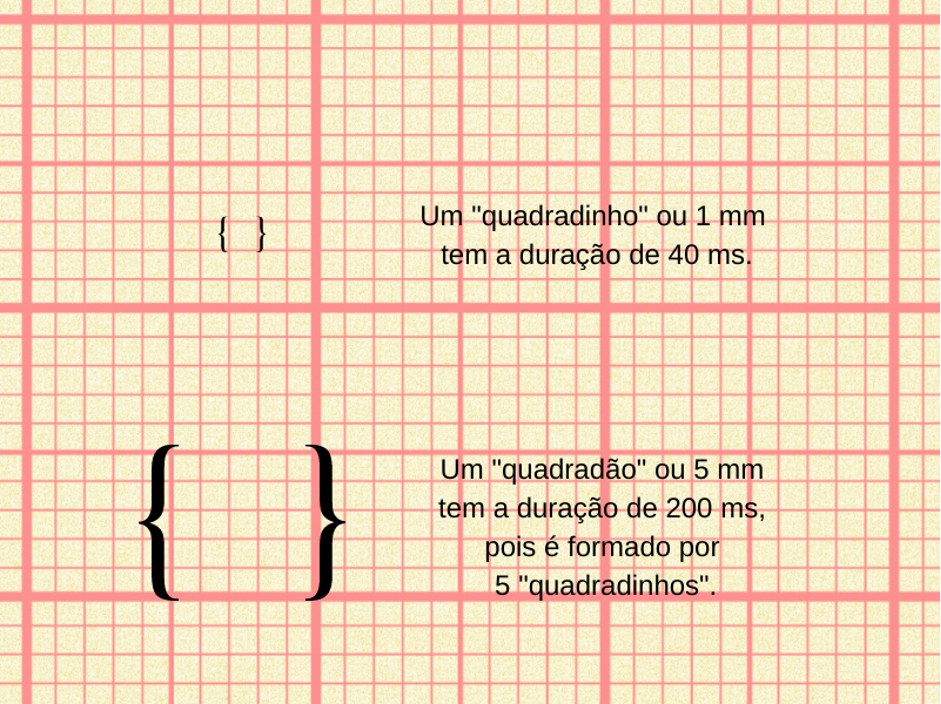

Configurado dessa forma, cada milímetro do traçado terá uma duração de 40 ms. Vamos entender?

Então, em outras palavras, um “quadradinho” tem a duração de 40 ms. Com isso, a gente consegue definir uma outra referência. O “quadradão”, que é o que vemos com uma linha mais grossa no papel, é formado por cinco quadradinhos. Portanto, a sua duração é de 5 x 40 ms = 200 ms. Vamos ver na figura abaixo a representação do quadradinho, do quadradão e os seus significados:

Figura 2: As referências de duração que o papel milimetrado permite avaliar em exames realizados com velocidade de 25 mm/s.